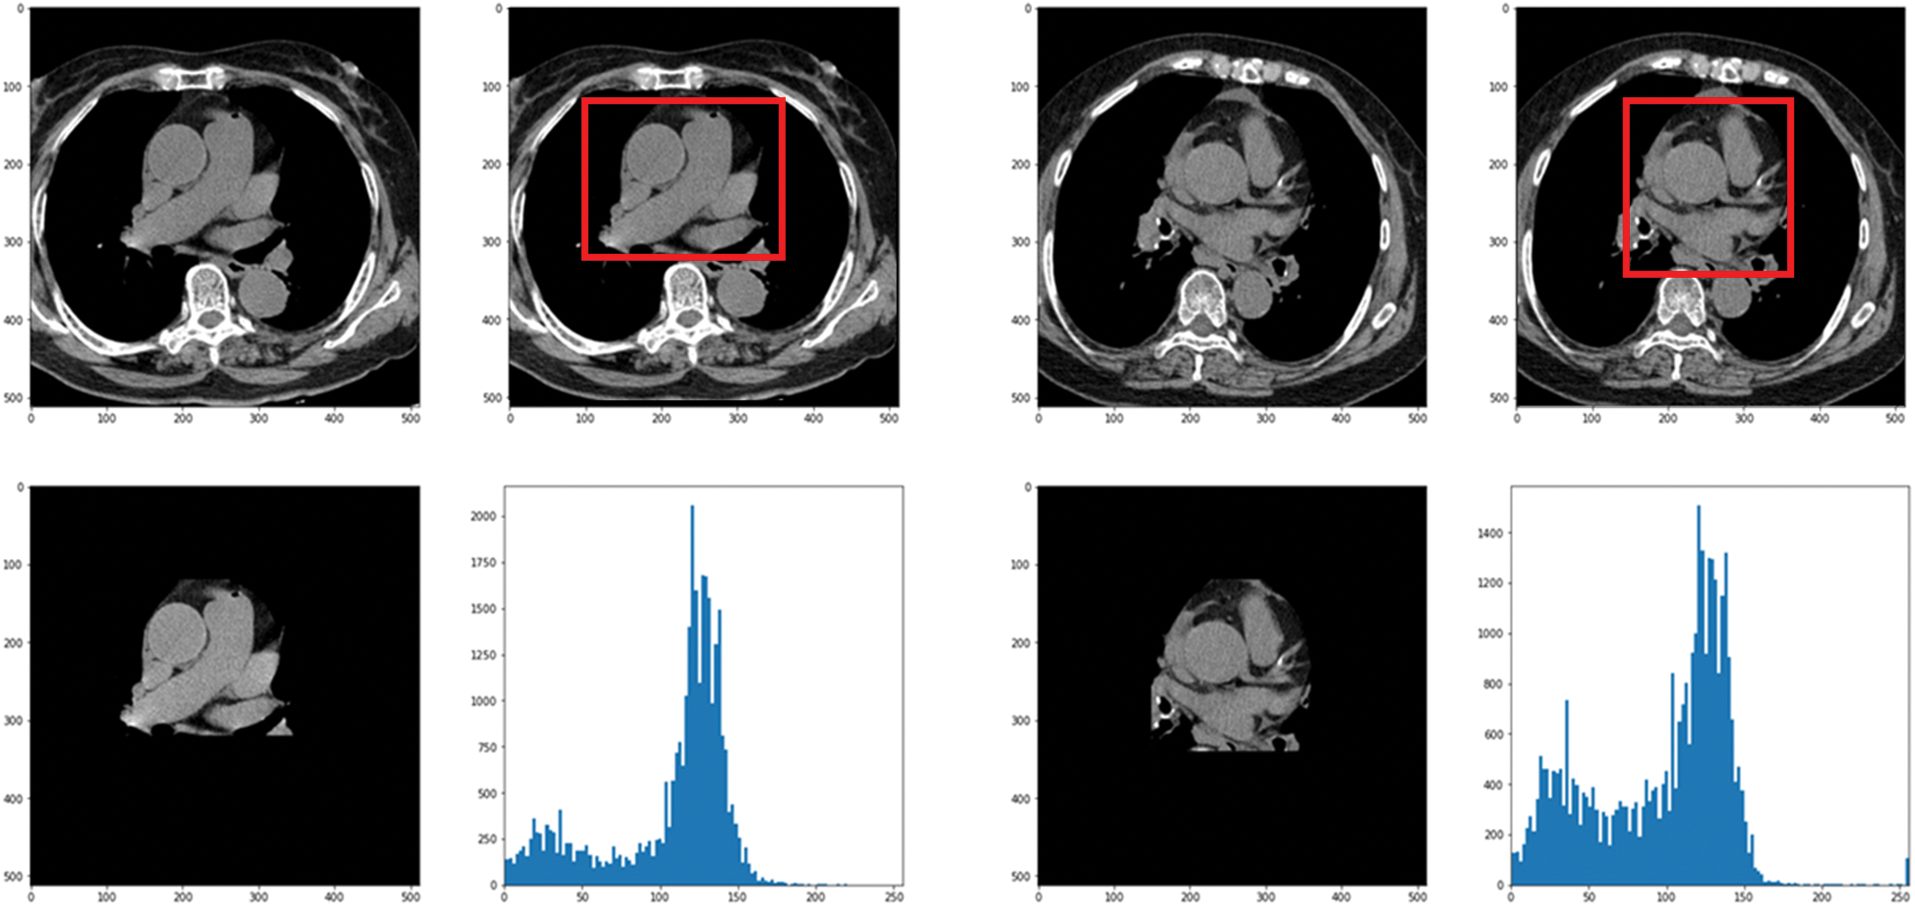

In this paper, the chest CT data has been divided into a ten-image dataset for the original image, K-means Clustering, K-Clustering images with Grabcut, and cropped images from both methods as shown in Fig. 4 were used, and K-means clustering and Grabcut were applied to the original image. In total, 2,400 chest CTs were used, 2,400 images through the original and K-means clustering algorithm and 2,400 data through K-means clustering and Grabcut were used. Ultimately, 7,200 pieces of data were used as a result of reducing the calcium-containing area and the calcium-free area to allocate the same ratio. The images were divided into subdivided images, and all image folders were divided into a group in which calcification had progressed and a group in which calcification had not progressed. The idea of not training parts other than the heart in the preprocessing stage came to mind when we expressed the histogram using Opencv as depicted in Fig. 5. However, at first, there were too many dark areas, so I removed 0 from the range [0:256] and changed it more dynamically. After excluding 0, the data of the normal group and the data that had undergone calcification showed a large difference in values at 256, and when the ROI was set and checked as shown in the figure, the progress of calcification could be seen more clearly, OpenCV supports ROI operation for some functions, but at this time, mask image must be passed as a factor. A mask is a binary image made up of zeros and non-zero. That is, 1 to 255 are treated as the same value. When a mask is applied to an image, all pixels that are 0 in the mask are set to 0 in the output image. It can be implemented using multiplication or AND operation for pixels, but the latter is usually faster. If the ROI is set through this masking operation and only the heart area is drawn as a histogram, it will appear as shown in Fig. 6. The value for 256 was 0 for a normal heart, and the value for 256 increased for data with calcification. So, we thought that if we learned by detecting only the heart region, the accuracy would increase because the feature of other organs was not included. The flowchart is described in Fig. 7.

Figure 6: Result when a histogram is drawn with only the heart region by setting the ROI